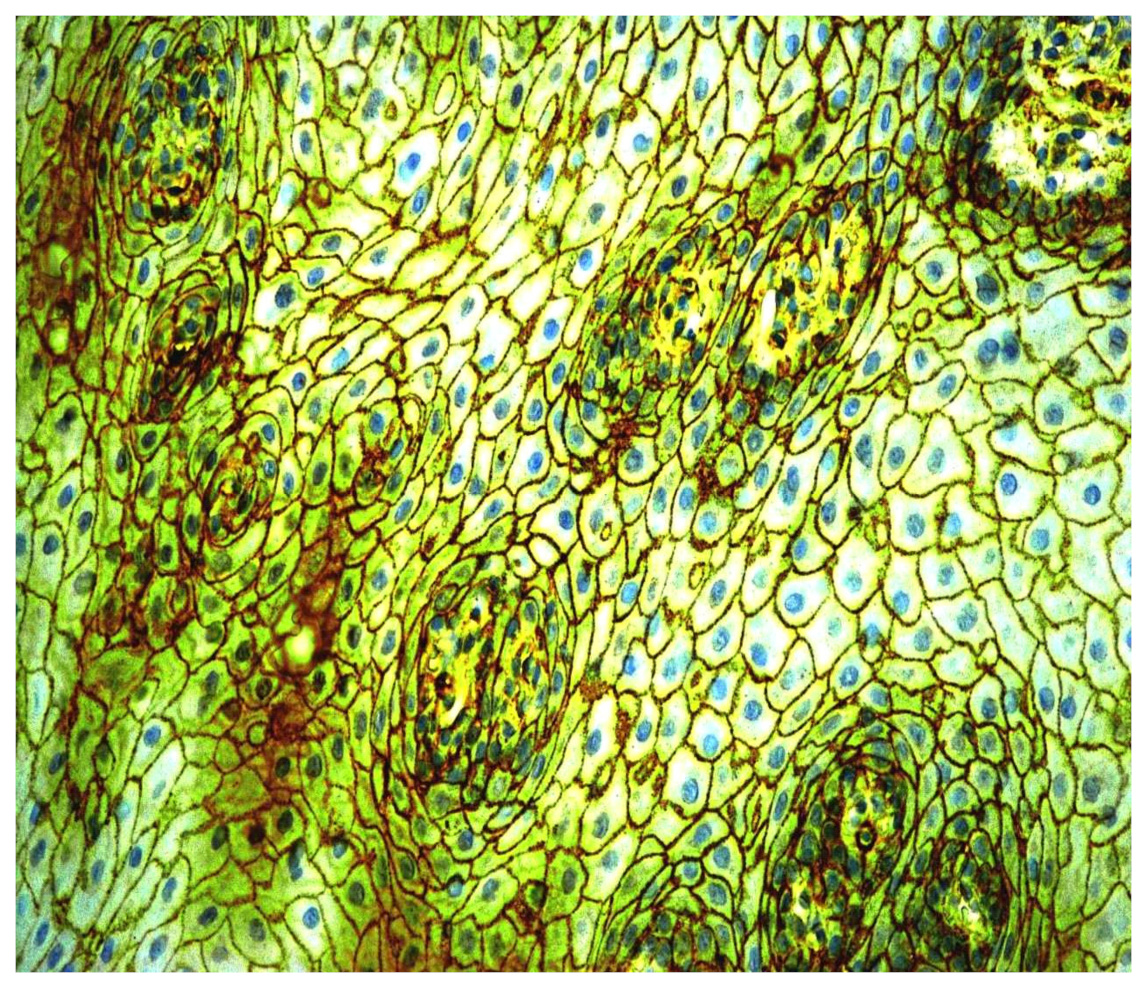

3.3. Immunohistochemical CD9 Antigen Characteristics

- Dzudzilo, M.; Kleina, R.; Čēma, I.; Dabuzinskiene, A.; Svirskis, Š. Expression and Localisation of CD44 Antigen as a Prognostic Factor of Oral Leukoplakia. Proc. Latv. Acad. Sci. Sect. B Nat. Exact Appl. Sci. 2021, 75, 68–74. [Google Scholar] [CrossRef]